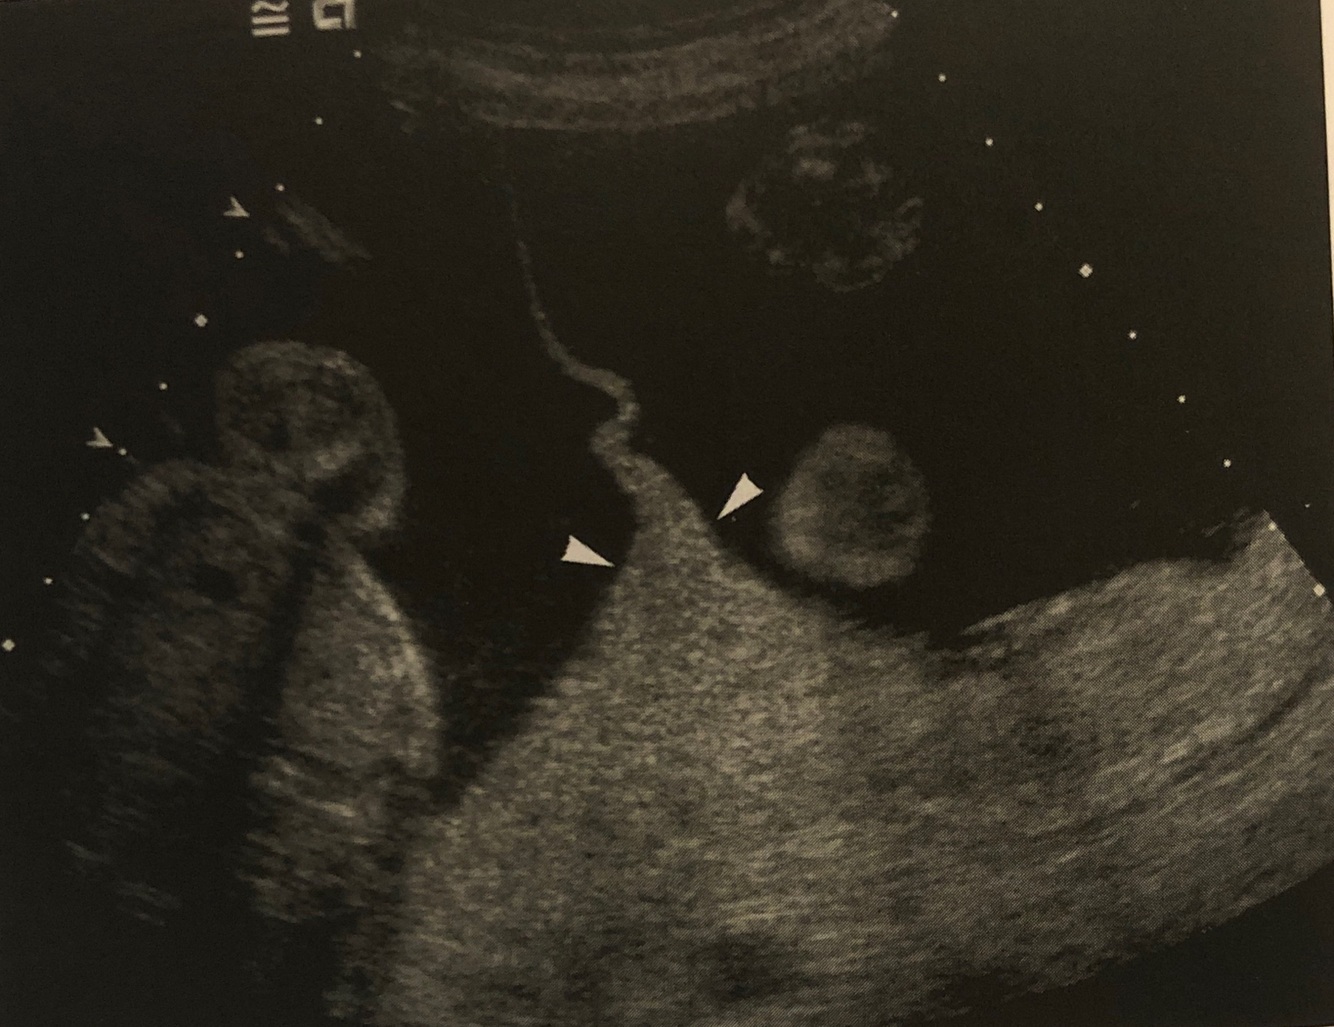

17

Q

What sign is this? What does this prove?

A

Lambda/twin peak/delta sign. Proving dichorionic